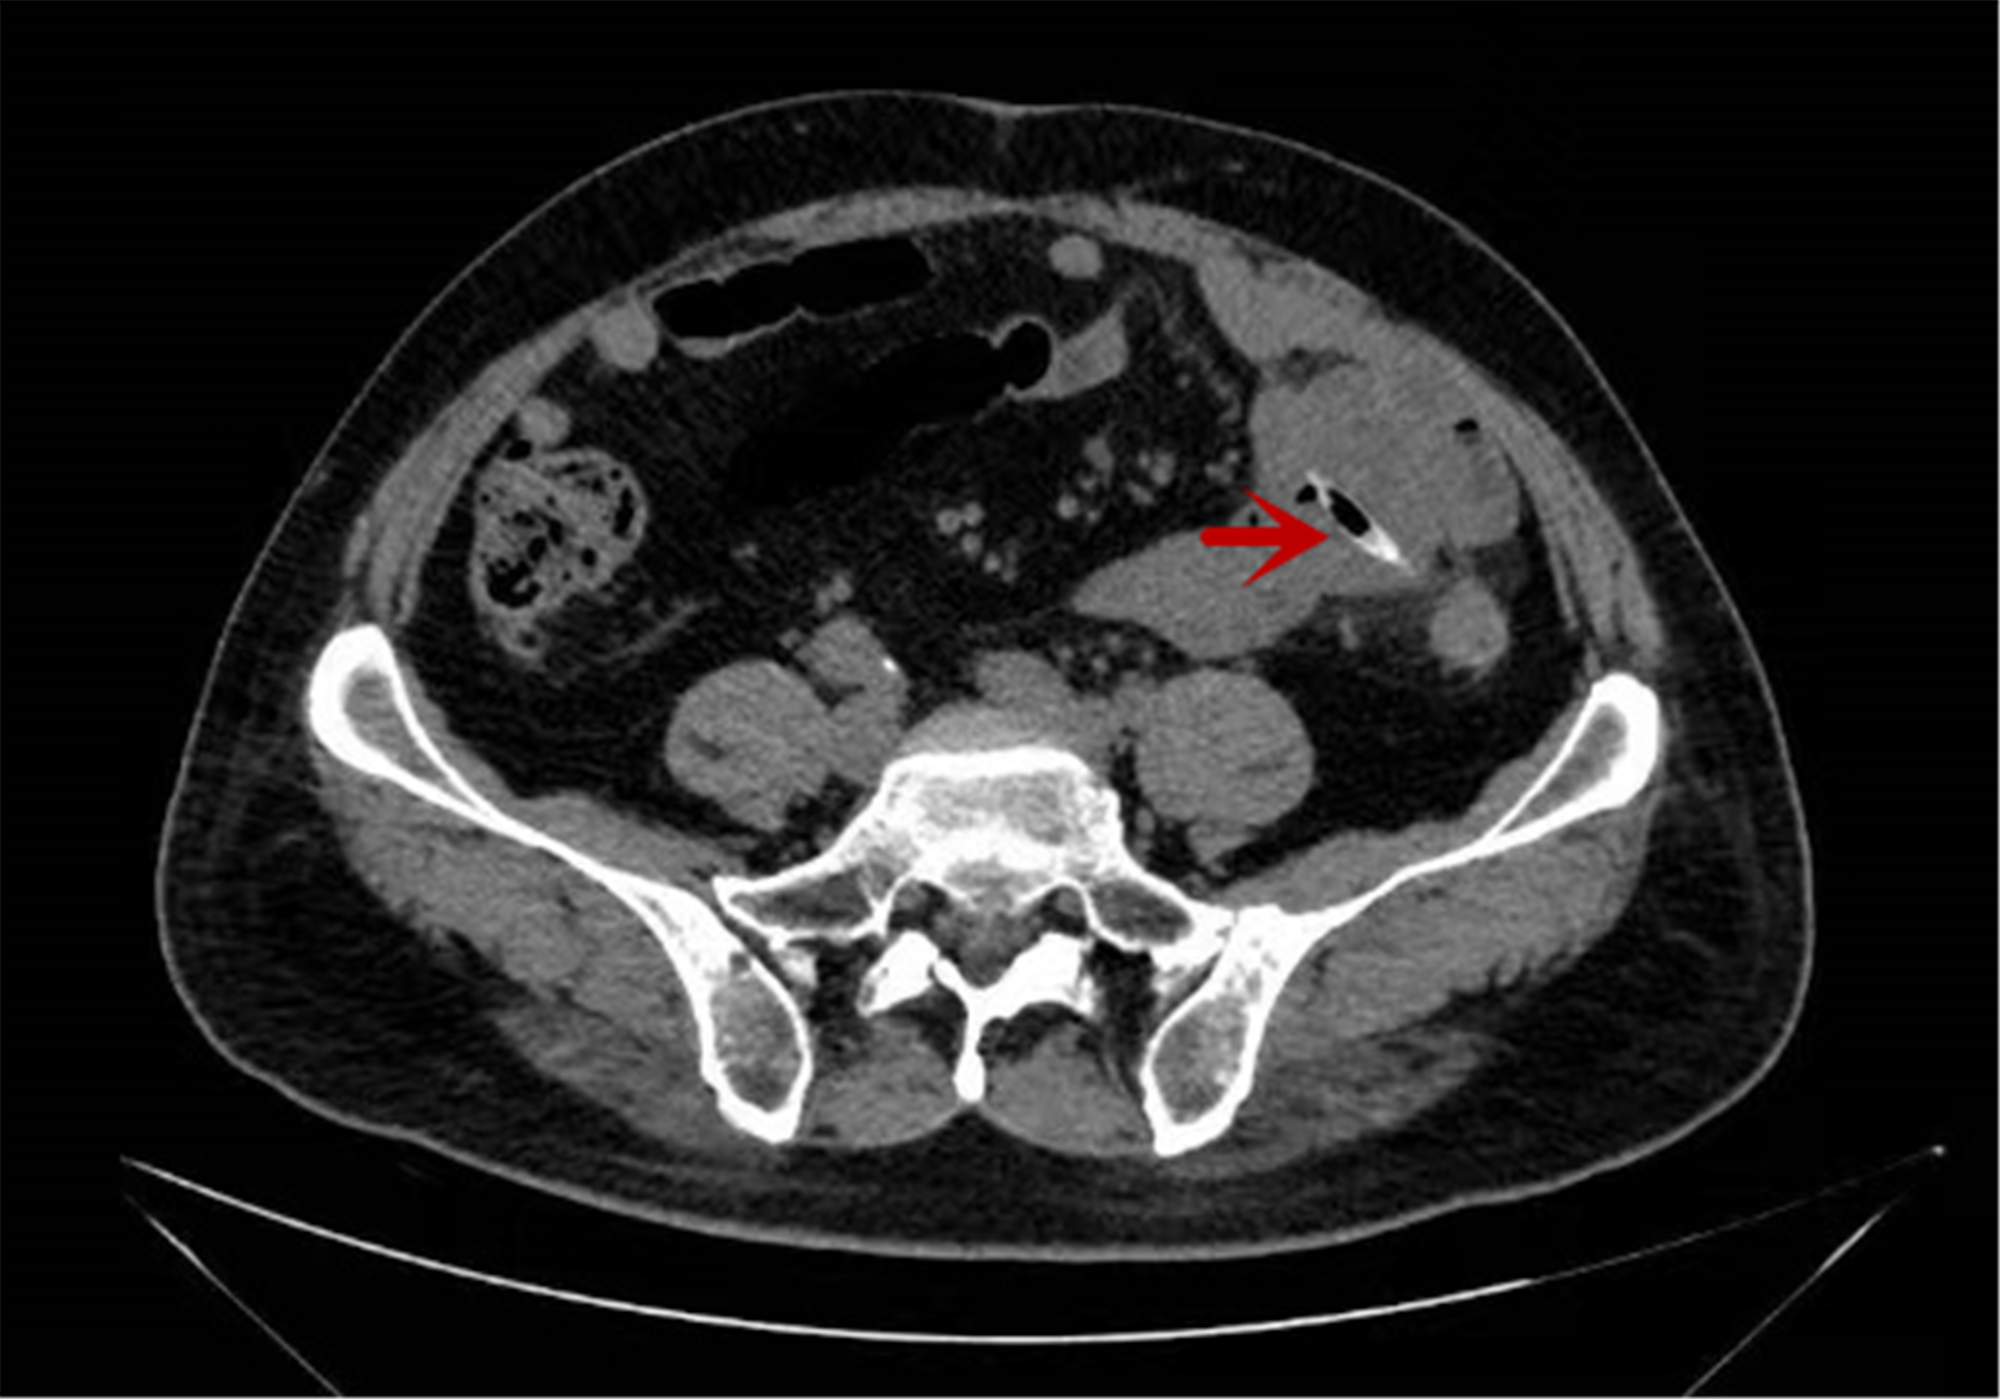

为寻求明确诊断,李大爷找到了北院肛肠外科负责人程伟才。程伟才在详细问诊和阅片中发现,其腹部CT存在异常阴影,高度怀疑腹腔内异物残留。尽管患者自述无外伤及明确异物吞食史,为彻底解除病痛,医生决定行腹腔镜探查术。

医生发现腹部CT存在异常阴影,高度怀疑腹腔内异物残留。